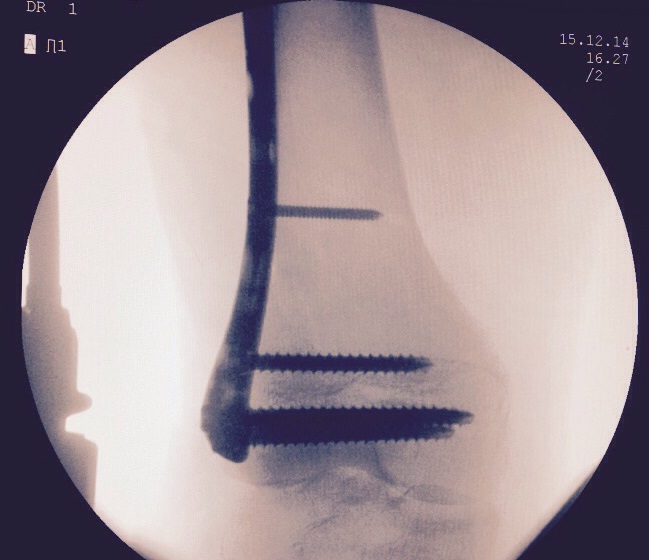

Images Gallery